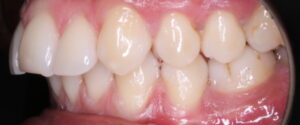

a) En la arcada superior: exodoncias de primeros premolares superiores( tamaño dental: 7,5mm) y uso de anclaje absoluto ( mediante dispositivos de anclaje esquelético), ya que la protrusión del incisivo superior era de 10,5 y la norma se sitúa en 4.

A eso hace referencia al número 7,5 de la parte superior y la flechita hacia atrás, que indica la retrusión que debemos hacer de los incisivos superiores. Dicho de otra manera el espacio que se obtiene de la exodoncias de 14 y 22, se consume al llevar los incisivos superiores hacia atrás. De ahí, el uso de microtornillos, para que los molares superiores no se mesializen.

B) En la arcada inferior: la situación es distinta, ya que el paciente, tiene ausencia de 34 y 44. Además  cursa con una desviación de la línea media inferior hacia la izquierda de 3mm. También, en el cuadrante 3, se ha consumido el espacio de dicha pieza ausente, por inclinación corono mesial de 36 y 37 por lo que nos vemos en la necesidad de recuperar ese espacio perdido. Al realizar el estudio, nos damos cuenta que la necesidad retrusión del incisivo inferior es 3,75. ( la norma es 1, y están en 4,7). Además analizamos, la curva de Spee, y para nivelarla necesitamos 0,75 por hemiarcada.